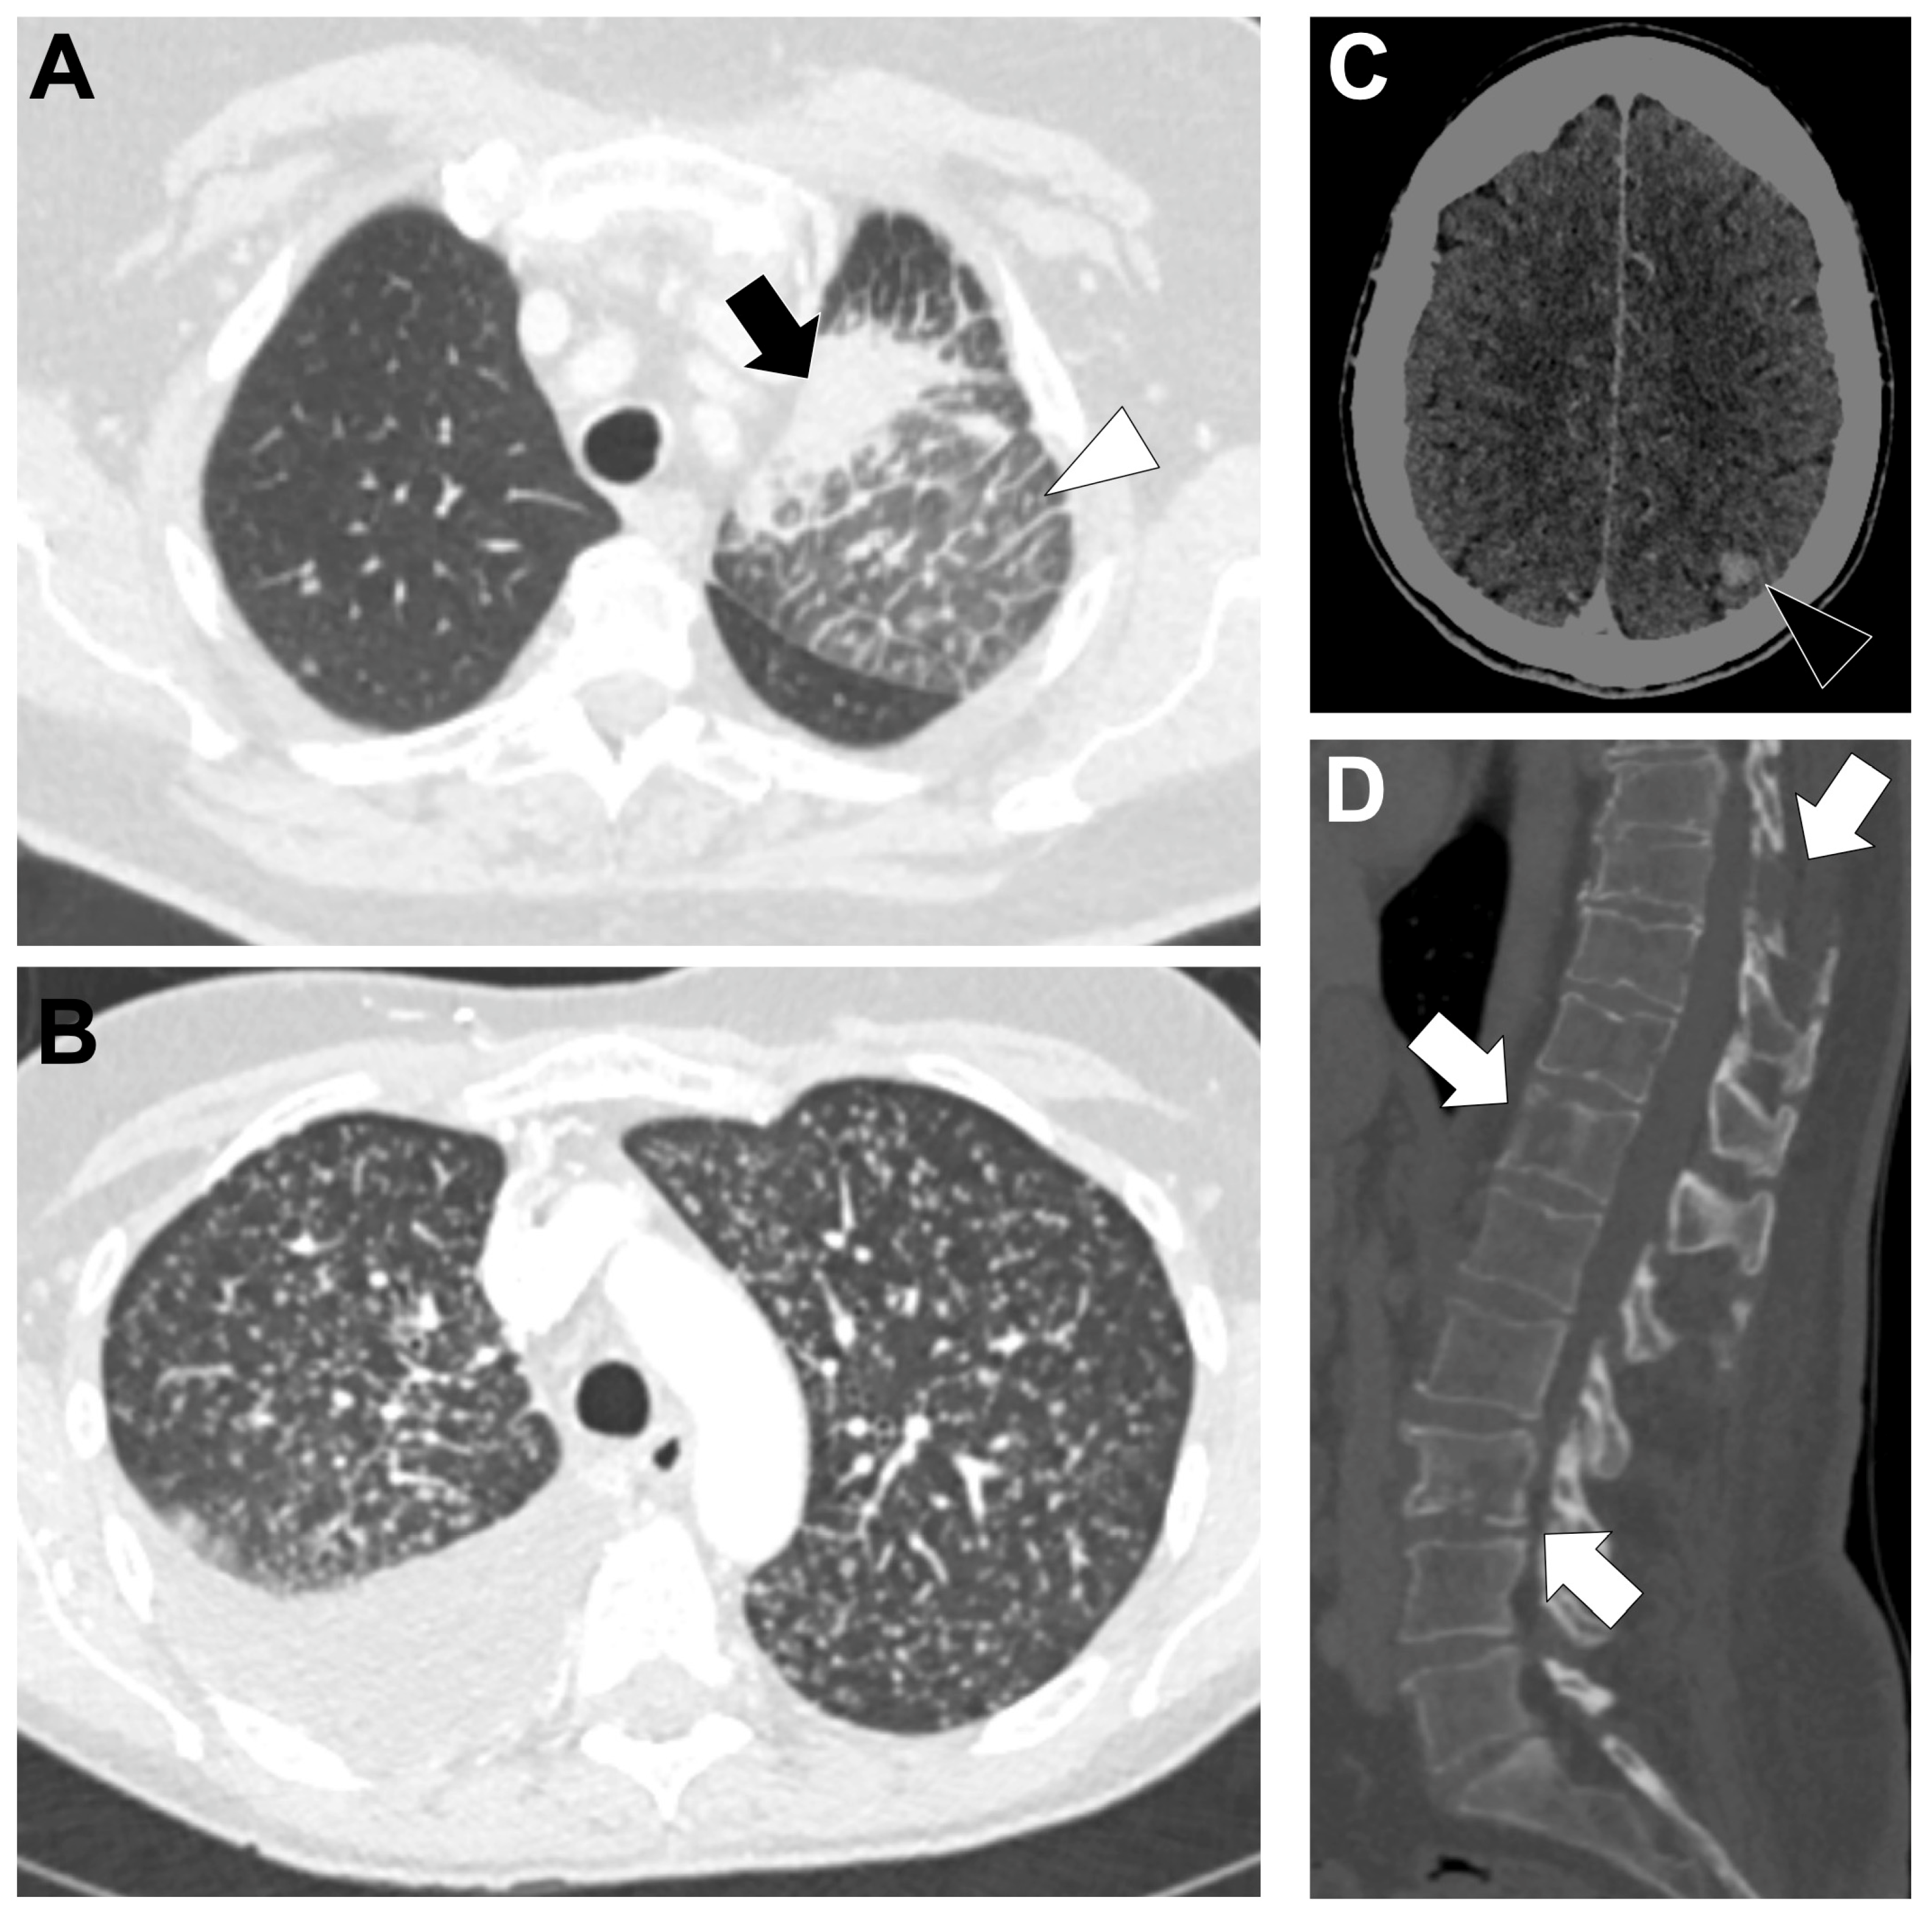

3.8. HER2-Altered NSCLC (Figure 8)

3.8.2. Radiological Characteristics of the Primary Lung Lesion in HER2-Altered LUAD

3.8.3. Metastatic Pattern in HER2-Altered LUAD